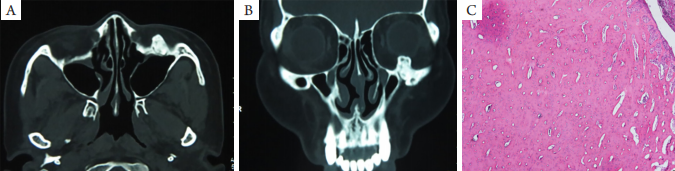

图1 骨瘤眼眶CT图像和病理学表现

(A)水平位CT示左眶下壁密度增高骨硬化影像,密度均匀,有明显边缘,肿瘤边缘规则,无溶解破坏;(B)冠状位CT示眶下壁骨样密度影,向眶内突出挤压眼球;(C)镜下见少量纤维结缔组织和骨小梁组成(HE,×5)。

发生于眼眶骨的肿瘤发病率较低,临床少见。由于眼眶骨与眼球等眶内容物关系密切,所以眶骨的肿瘤病变大多以眼球位置及运动改变、视力变化、眶周肿物等症状就诊,若为恶性肿瘤则还可能伴有全身转移的相应表现。在一些起病隐匿的骨肿瘤中,初期也可能并无体征和表现,大多为偶然发现或当肿瘤发展到一定的程度,累及周围组织时才会出现相应的临床症状。骨瘤,又名骨细胞瘤,是一种比较常见的骨源性良性肿瘤,肿瘤被分为象牙型、成熟型和混合 型3种类型。好发于额窦和筛窦,偶见于眶壁骨骼,一般无明显的症状,当肿瘤增长蔓延至眶内时可出现眼球运动障碍、斜视和眼球突出等症状。肿瘤可向骨表面和髓腔生长,可突入窦腔、眼眶,使颅面畸形,骨瘤增大极缓慢[2-3]。病理见瘤体主要由异常排列的成熟板层骨组成,因此大量的骨成分使肿瘤在CT上一般表现为骨表面边界清楚,形状规则,密度均匀的高密度影,与眶骨显影类似。